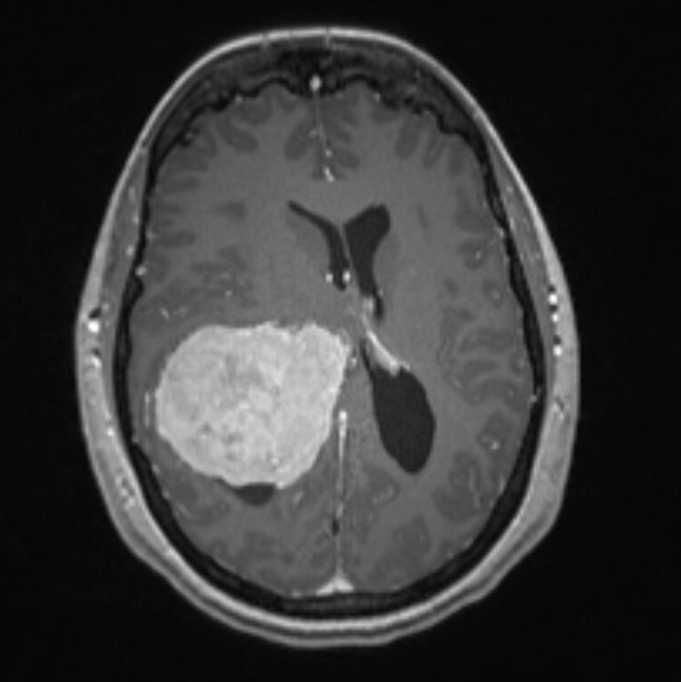

Sollte ein CT erfolgt sein (z.B. Schockraum bei schweren SHT, siehe hier), so können ICP-Anstiege wie folgt darstellbar sein: Herniation, Ventrikelkompression, Mittellinienshift, Verstreichen der Sulci, Verlust der Grau-Weiß-Differenzierung (indirekter Hinweis auf Hirnödem). Hier könnt ihr ein paar Originalbilder aus meiner Tätigkeit begutachten. Beachtet die Kompressions- und Raumforderungsphänomene.